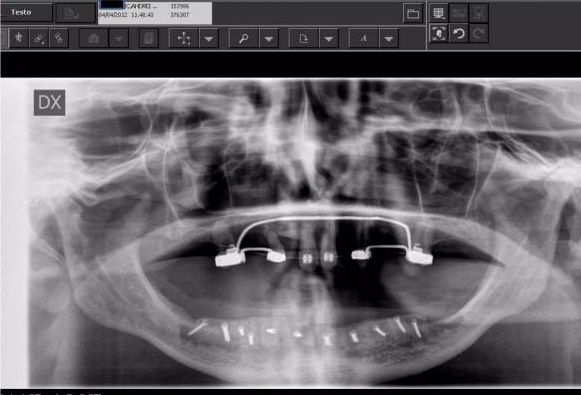

Per poter procedere con l’intervento a carico immediato è necessaria una valutazione del Prof. Giulio Gasparini specialista in Chirurgia Maxillo Facciale che mediante una prima visita iniziale, eseguendo un’ anamnesi ed esami radiografici preliminari, è in grado di determinare se ci sono le condizioni favorevoli dell’osso, in cui verranno inseriti gli impianti. Da questo momento l’esecuzione degli impianti a carico immediato e alla consegna dei vostri nuovi denti è solo una questione di poco tempo.

La visita iniziale ha in genere una durata di circa 30 minuti. Sarà il chirurgo ad accoglierti per procedere con una visita accurata in ogni aspetto: ti sarà richiesto di compilare una anamnesi medica che ci permetta di conoscere al meglio il tuo stato di salute e verranno svolti gratuitamente tutti gli esami radiografici necessari ad approfondire la tua situazione.